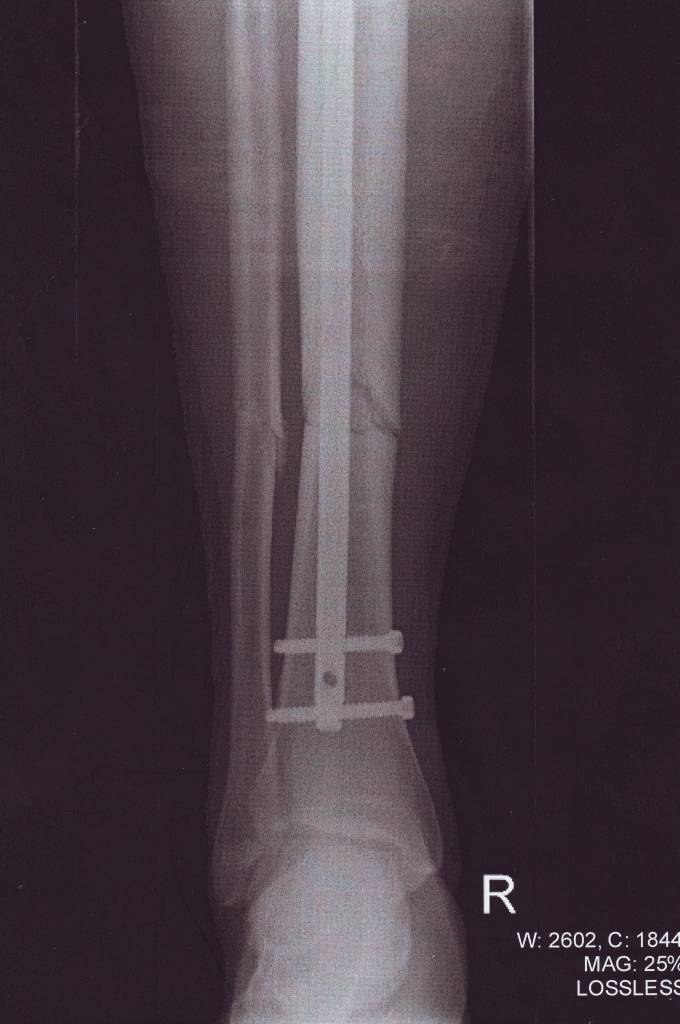

En fantastisk dag i offpisten med 20 -25 cm snö slutade så här efter att jag skränsade in i en sten med tvärrställde skidor i dimman.. Det gjorde faktisk mindre ont än jag hade föreställt mig... Det var den sesongen! :(

- Fotograf: Ringerike Sykehus

- Kamera: Avancerad Röntgenkamera